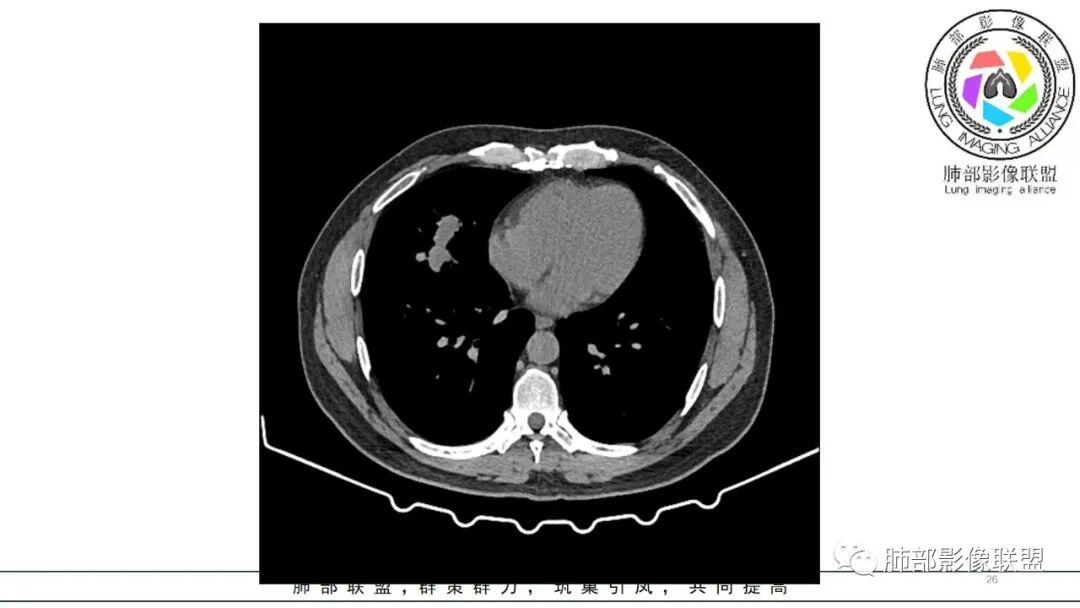

双肺多发实性小结节,边清,多位于胸膜下。右肺中叶不规则实变影,沿支气管血管束走行,似有跨叶。

双肺胸膜下多发结节,部分结节内可见空洞影。右肺中叶斑片影(类似指套征),并可见右肺中叶支气管壁增厚。看到病史的时候,看到鼻窦炎,中耳炎。想到如果与鼻窦炎相关,1.有GPA,但是GPA,典型是鼻,肺和肾的病变,有鼻窦炎,软骨受累,眼睛受累红肿等。晨读没有提到肾方面损害。另外,晨读的结节更多表现为血播,与支气管血管束关系不大。如果是GPA应该主要是与血管相关,与支气管血管束密切相关。2.和鼻窦炎有关的真菌感染,曲霉?但是肺内病变难以一元,右肺中叶与气道相关,双肺多发结节与血道相关。不是说一般气血难以兼容。还有就是如果是曲霉的指套,密度偏低了。3.按两肺多发结节方向考虑,隐球菌需要鉴别。总之,晨读隐球菌>GPA>真菌曲霉

男,47岁,咳嗽咳痰发热三天,既往中耳炎病史。CT示双肺多发随机分布小结节,多位于胸膜下,部分伴小空洞,右肺中页不规则实变影,沿支气管血管束走行。实验室检查血沉,CRP增高。综合考虑为感染性病变,隐球可能,鉴别GPA

双肺多发结节,以胸膜下分布为主,形态相似,边缘较规整,少部分边缘晕征,无分叶毛刺;右肺中下叶多结节融合并实变影,边缘平直、U形征,跨叶。

病灶与支气管血管束无关,定位肺实质来源病变,考虑良性病变,炎性肉芽肿病变:隐球可能。

中年男性,咳嗽咳痰低热3天,偶有血痰。有鼻炎、中耳炎病史。右中叶病灶呈指套样,跨右下叶,叶间胸膜牵拉移位。两肺胸膜下多发结节灶,边缘模糊见晕征,部分呈空洞结节。白细胞计数及CRP、血沉稍高。跨叶的指套样病灶有小细胞肺癌的影像特点,两肺多发结节,但近肺门、纵隔无肿大淋巴结,不符合小细胞肺癌的转移特点,考虑非肿瘤病灶。没有典型的多形态、未见树芽征,肺结核可能性小;两肺胸膜下病灶有晕征,存在隐球菌病可能,但右中下叶的主病灶形态在隐球菌病中罕见;有鼻炎病史,肺内病灶存在血管炎可能;患者为银行职员,应该经常接触纸币,有血痰症状,主病灶呈指套样,两肺多发晕征及空洞,存在曲霉菌感染可能。综上考虑肺曲霉菌病可能,鉴别血管炎、PC、TB。

右中叶病变+双肺多发胸膜下为主的结节,有中耳炎和鼻炎病史,似乎提示GPA,但是,右中叶病变像粘液栓,提示是气道来源,这个征象不大支持GPA。嗜酸不高,IgE不高,不支持ABPA和寄生虫感染,隐球表现有粘液栓征象的很少见吧?所以脑海里还没有搜索出更能解释这种影像的疾病,但总体印象,右中叶病变是气道来源病变,双肺胸膜下病变倾向于血道来源,病程较短,无典型恶性征象。抗菌素似乎有效,倾向于感染性病变,什么病原体?奴卡?结核?NTM?

有结节融合之感,类似隐球菌的融合

肉芽肿伴晕,分布符合。

然后这条,血管周炎的。。如果血流感染一般不是这个形态

他不是气血都可以,他是沿着血管周围的炎症

所以,位置都可以,但是形态可能会沿着血管的长

轴形成条状,或者包绕支气管周围。最后也容易有晕征,以及这个鼻炎。。

主要是形态,分布和晕征,+鼻炎这个提示

隐球菌,这个条状的一般会与胸膜平行,这一点不太符合,而且胸膜下结节分布太散没有融合,这一点不太像,所以排在第二位